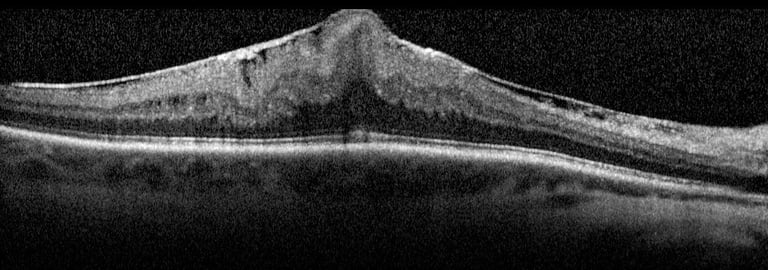

Optical Coherence Tomography (OCT): This non-invasive imaging test provides detailed cross-sectional images of the retina to detect swelling, fluid, or retinal tears.

2. Macular Holes

A macular hole is a small tear or break in the macula, the part of the retina responsible for central vision. Macular holes often develop due to aging, trauma, or underlying retinal conditions. Symptoms include:

In most cases, macular holes can be treated with surgery (such as vitrectomy) to repair the hole and improve vision. Early intervention can prevent further damage to the retina.